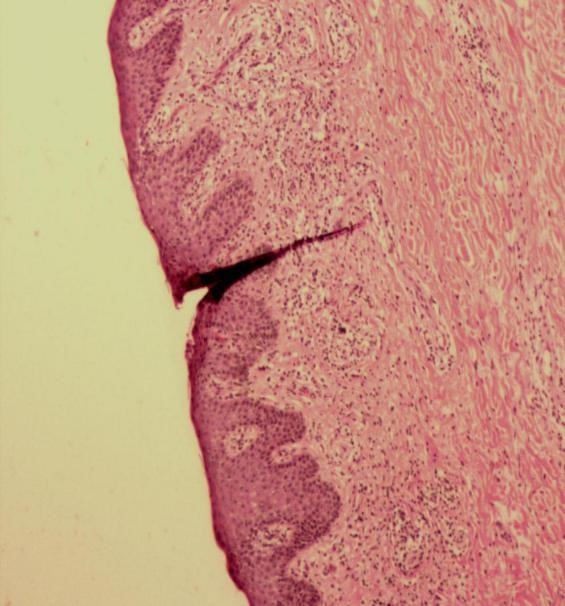

患者外院已行淋巴结活检,予病理会诊:“左腹股沟淋巴结”符合皮病性淋巴结炎。免疫组化:CD79a(B+)、BCL6(-)、CD3(T+)、Bcl-2(+)、CD68(灶+)、CD20(B+)、CD21(FDC+)、CD163(灶+)、CD43(T+)、CD5(T+)、CD10(-)、CyclinD1(-)、S-100(lagerhan+)、CD1a(lagerhan+)Ki67(+约5%)(见图3)。

图3